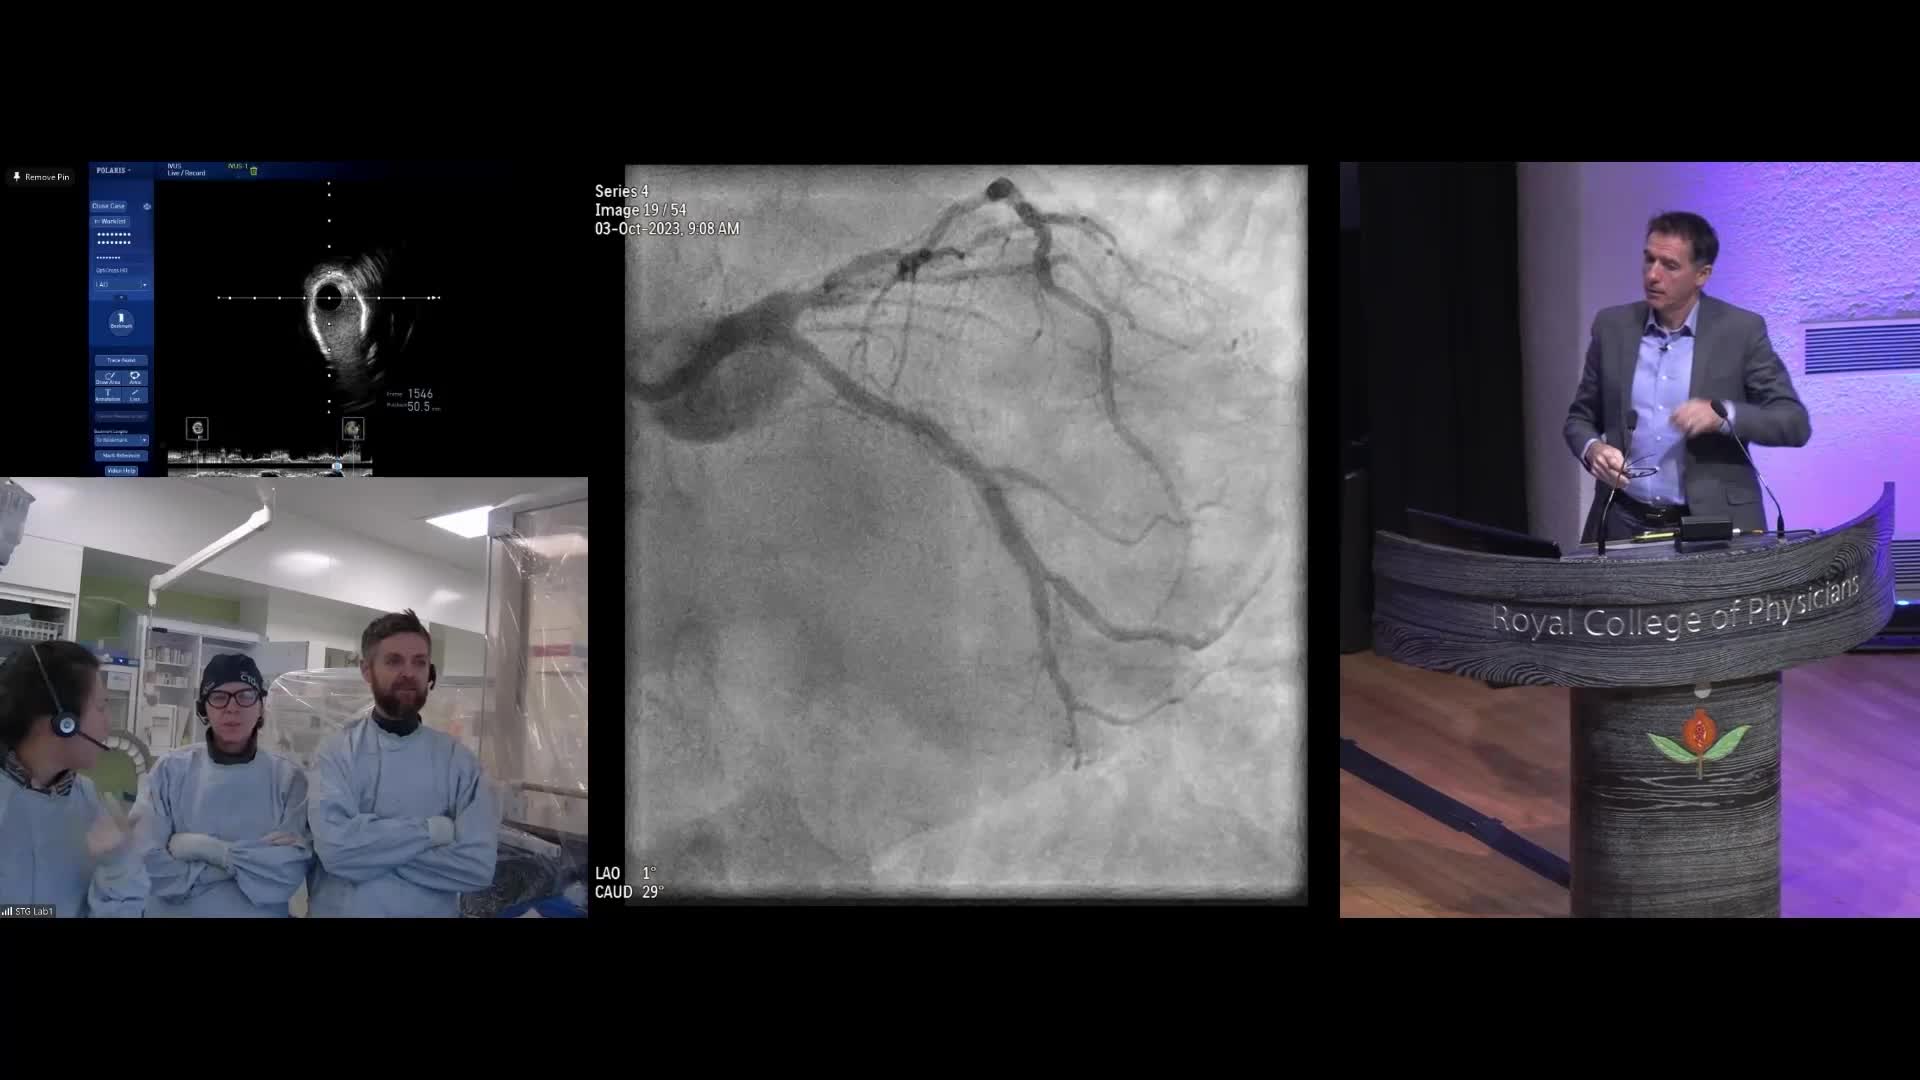

Session 4: High-risk and complex – too tough to treat?